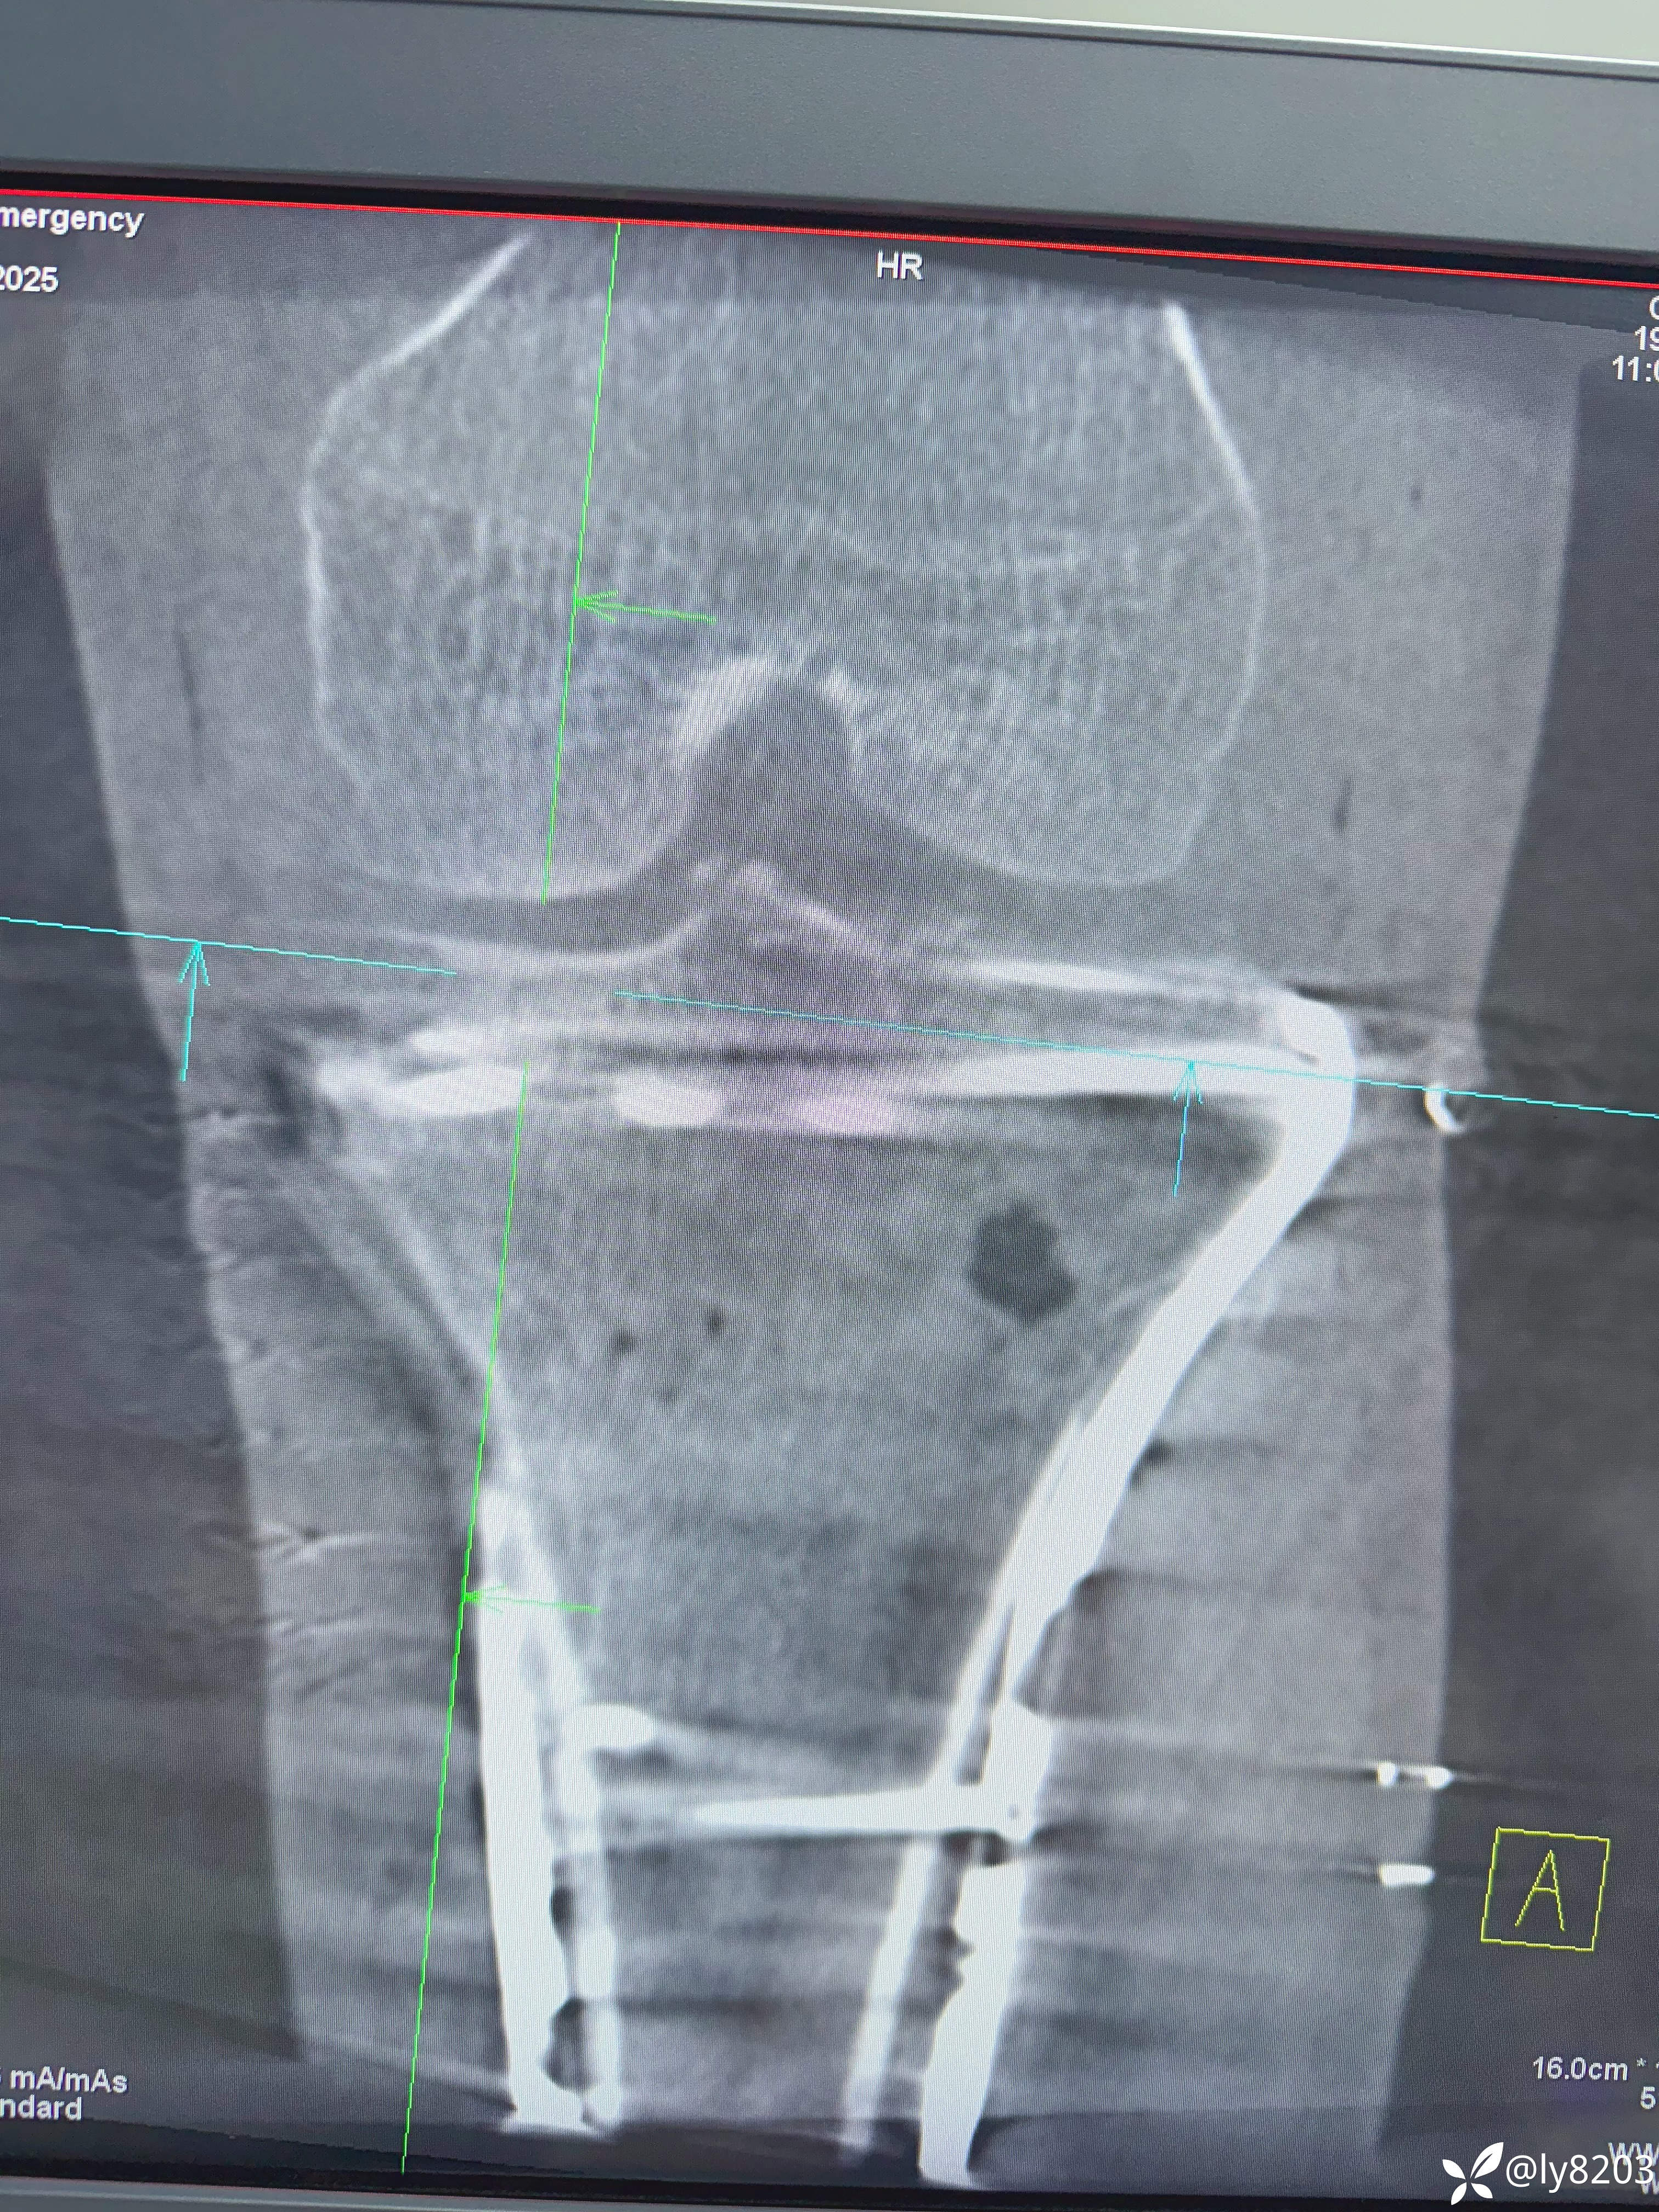

术后影像

术后平片

这个难点在后外侧游离骨块。按胡老师的方法,先将外侧平台用两个弯钳抬起,与前髁间棘对齐后克氏针固定,再从外侧副韧带后缘用骨拨托住并往前顶,从关节线用弯钳从前面抬,没成功,随即改变方案,用胡式顶棒外侧经皮顶,后侧骨块解剖复位,后缘与外侧平台丝滑对齐,克氏针固定。剩下就是常规操作了。以往都是大切口,截骨处理后外侧,胡教授的方法避免了切口大,创伤大。有利于加速康复。